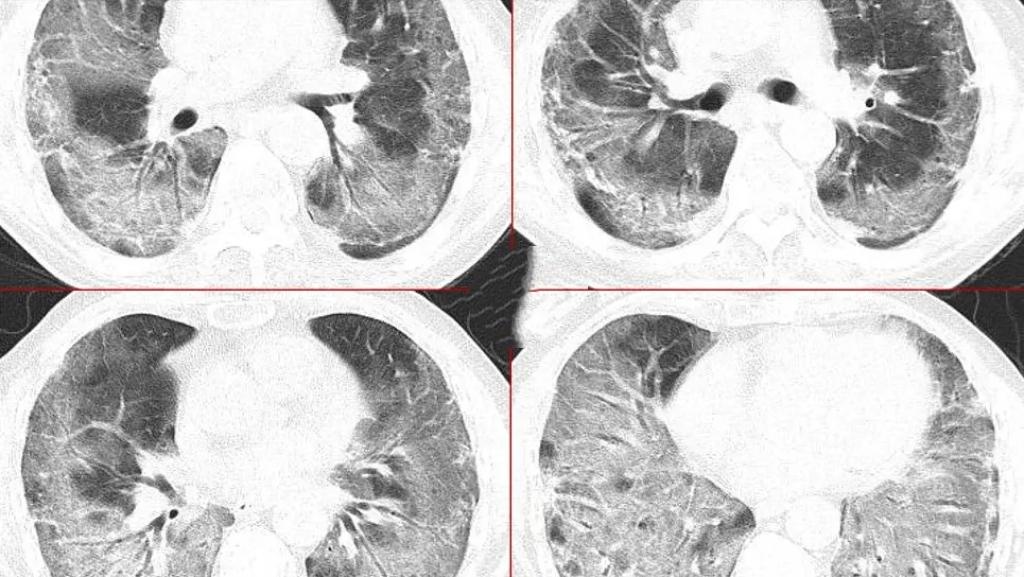

近日,河南4岁女童朵朵突发甲流合并细菌感染,24小时内病情急转直下,出现“白肺”并住进监护室。经紧急ECMO救治后转危为安。专家提醒,儿童免疫系统脆弱,甲流易继发细菌感染,出现持续高热、呼吸急促等症状需立即就医。预防甲流